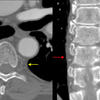

PA angio

Fig 2

Fig 3